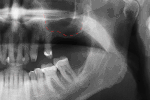

- с помощью рентгенографии изучаются качество и плотность костной ткани;

- проверяются окклюзия и артикуляция;

- при необходимости пациент получает консультацию по соблюдению правил гигиены;

- обязательно регистрируется износ коронок и пломб, закрывающих отверстия фиксирующих винтов;

- исследуется состояние зубов;

- выполняется профессиональная чистка зубов и имплантов от зубного камня. Гигиена является важнейшим фактором долгого срока службы зубных имплантов.